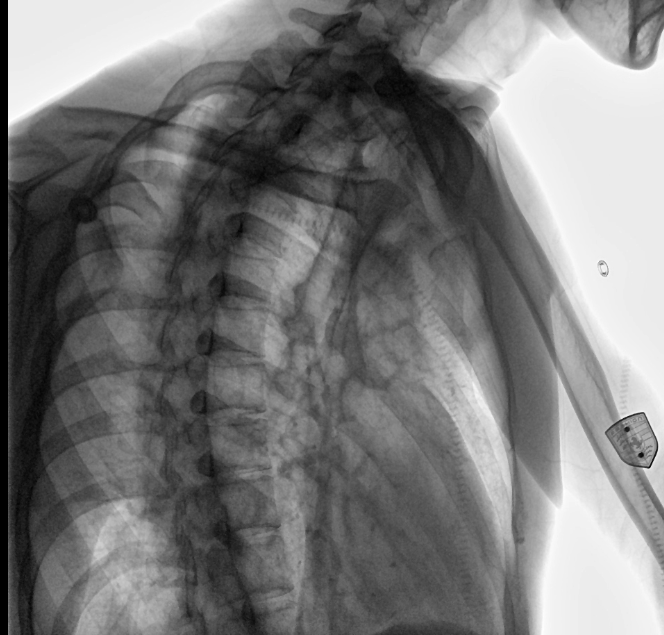

位于衡水市中醫(yī)醫(yī)院的動態(tài)平板數字化X射線系統(tǒng)DTP571具備高速高清點片功能。這是一款對放射科十分友好的產品。因為它把高速和高清點片結合,既能方便影像技師有效地抓拍需要的病灶的影像,又能給予影像醫(yī)生清晰的影像進行診斷。

動態(tài)觀察診斷,實時高清點片